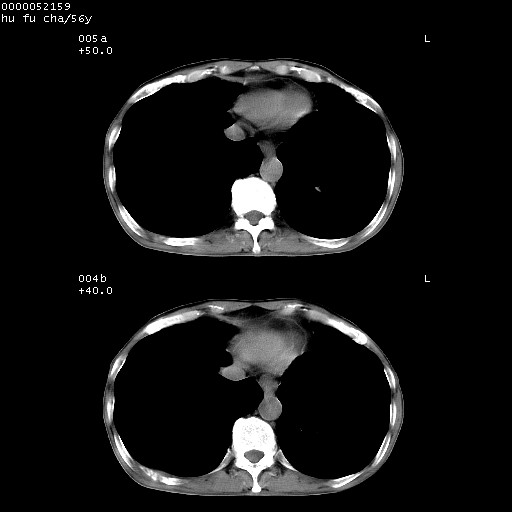

以下是引用zsl6918在2008-8-25 22:47:00的发言:[br]胸骨,胸椎及肋骨均可见多发转移表现,肝内低密度结节不除外转移。原发灶可能在右肺。双侧可见支扩表现。

以下是引用卜一在2008-8-26 8:02:00的发言:[br][br] 支持:肺癌并肺内,胸骨,胁骨,胸椎及肝内转移!另:左肺支气管扩张征伴感染! [br]

以下是引用zjzjr在2008-8-26 11:03:00的发言:[br]支持:肺癌并肺内,胸骨,胁骨,胸椎及肝内转移!另:左肺支气管扩张征伴感染!